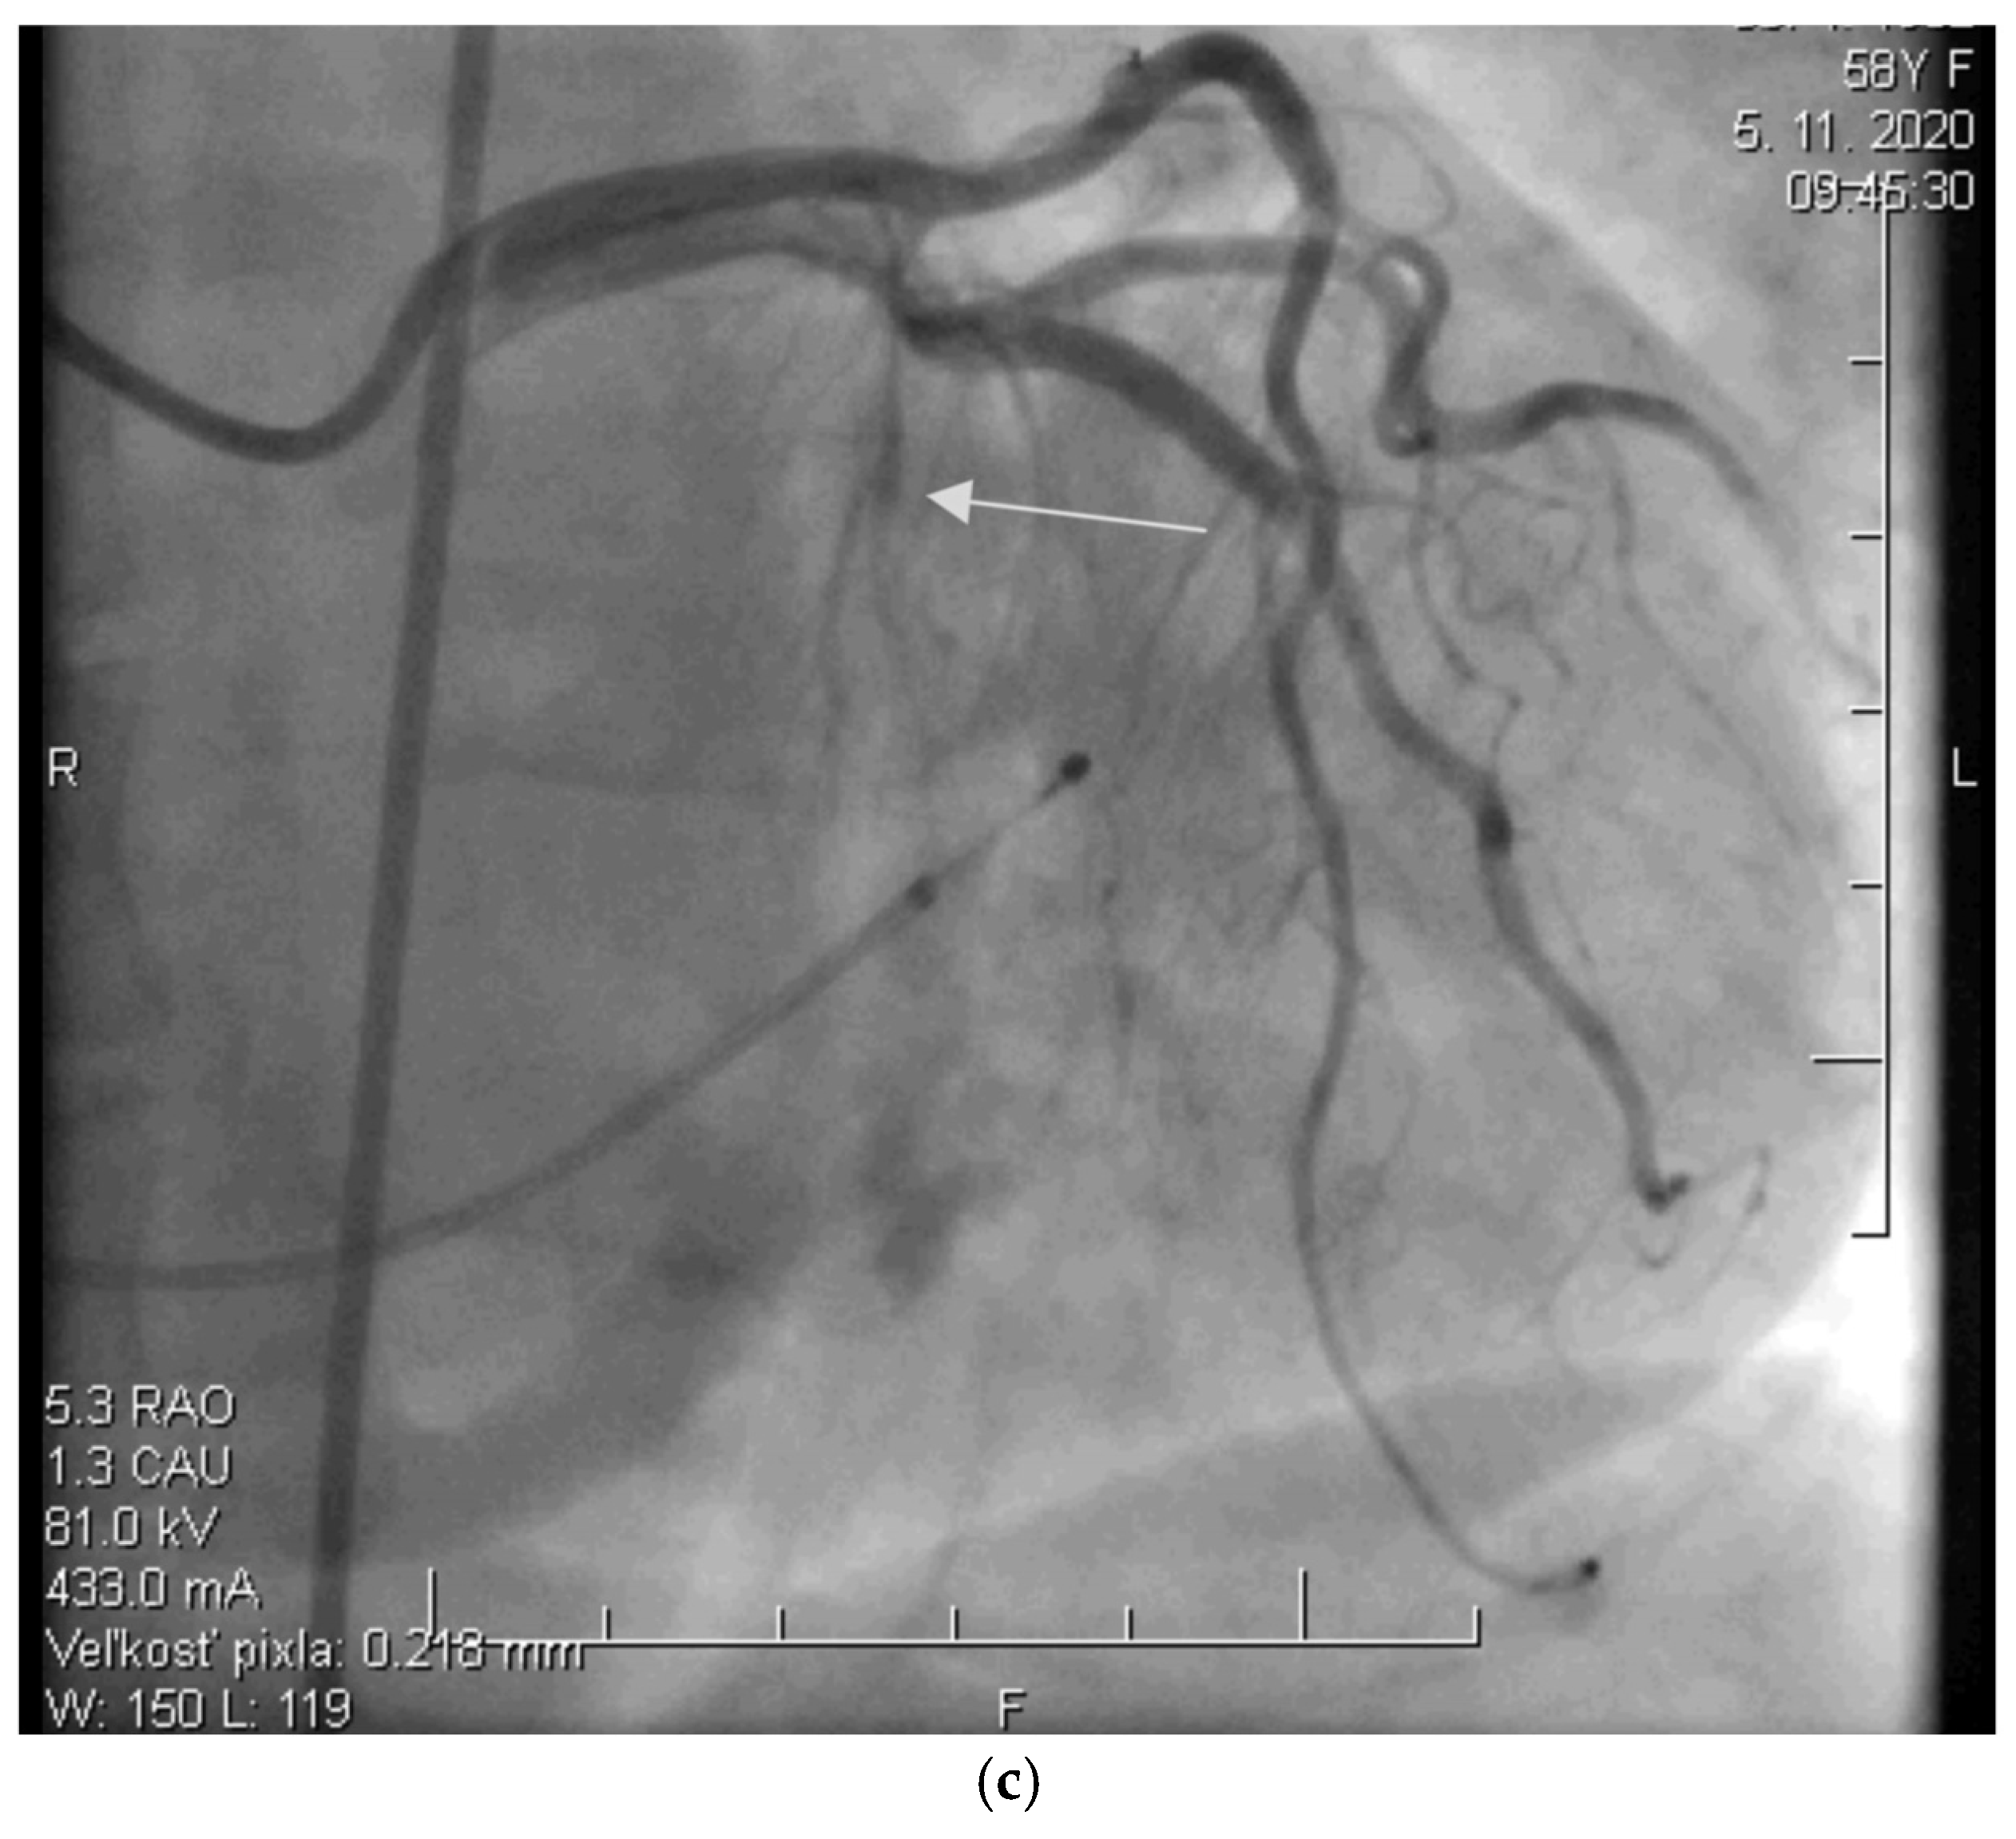

Before the procedure, a temporary pacemaker was inserted into the RV via a venous approach to prevent potential periprocedural conduction disorders. After the pacemaker was placed, selective injection of the left coronary artery was performed via a transfemoral approach to assess the anatomy of its branches (Figure 2a). Using a pigtail catheter introduced into the LV, the pressure gradient between the LV apex and the aorta was measured at rest and after provocation with a ventricular extrasystole, Valsalva maneuver, or, less frequently, nitrate administration.

Subsequently, a specialized over-the-wire balloon catheter was inserted into the septal branch supplying the area contributing to the LVOT narrowing (most commonly the basal interventricular septum. The balloon catheter was inflated to occlude the lumen of this vessel, followed by the injection of an echocontrast agent and echocardiographic assessment of the perfusion area and localization of the selected septal branch (echo-guided approach). After identifying the appropriate septal branch, 96% alcohol in a volume of 2 mL was administered uniformly to all patients according to internal protocol (Figure 2b).

Ten minutes after the alcohol application, the balloon was deflated, and the residual pressure gradient between the LV apex and the aorta was measured at rest and after the aforementioned provocative maneuvers. To conclude the procedure, a selective injection of the LCA was performed to confirm the ablation of the septal branch and exclude potential alcohol leakage into other parts of the coronary circulation, which could cause the no-reflow phenomenon (Figure 2c).

Figure 2. (a) Angiographic image of the left coronary artery showing a septal branch (arrow) (photo and copyright: T.P.). (b) Administration of 96% alcohol into the septal branch using an over-the-wire (OTW) balloon catheter (photo and copyright: T.P.). (c) Final effect of ASA with Closure of the Septal Branch (photo and copyright: T.P.).